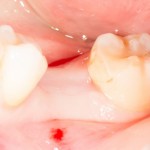

Простая клиническая ситуация (ключевое слово «простая»).

Отсутствует один зуб, клинические условия идеальные: это не эстетически значимая зона, объем костной ткани и прикрепленной десны в пределах допустимого. Зуб удален мной около полутора месяцев назад, то есть и пациент, и эта область мне знакомы.

У меня есть набор круговых мукотомов. С помощью мукотома делаем разрез слизистой оболочки.

То есть, друзья — и это очень важно, — разрез все же есть. просто он не линейный, а круговой. Вот и верь после этого рекламе))).

Кружок из десны мы убираем.